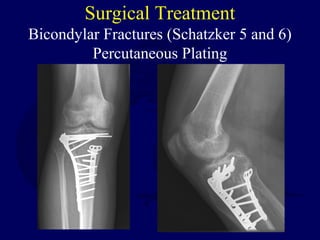

Surgical Treatment

Bicondylar Fractures (Schatzker 5 and 6)

Percutaneous Plating

Posteromedial Approach